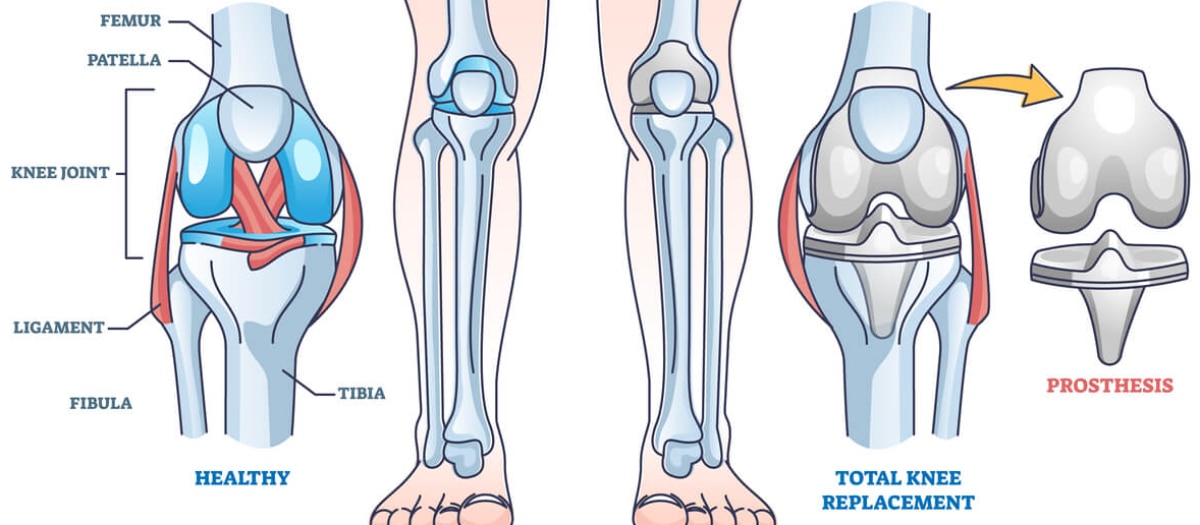

Joint reconstruction surgery is a valuable option for individuals who are experiencing joint pain and dysfunction due to various factors, including aging, wear-and-tear, or injuries. When less invasive treatments like injections and physical therapy are no longer effective, joint reconstruction surgery can provide relief and improve the quality of life.Total Knee Replacement (TKR):Total Hip Replacement (THR)Total Shoulder Replacement (TSR):Total Ankle Replacement (TAR):Elbow Replacement Surgery:Hand and Wrist Joint Reconstruction